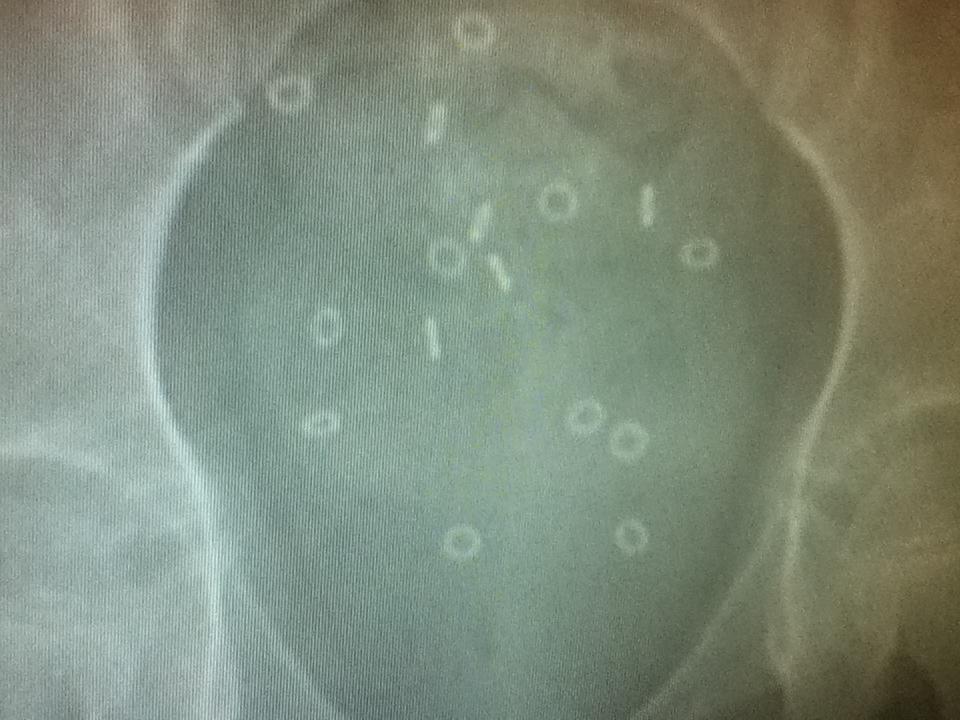

The image above is K’s lower abdomen 5 days after ingesting the markers. They should be mostly, if not all, gone by the 5th day after ingestion. They are basically all present. Dr. C said, “Well, now we’ve confirmed she has a problem from above, as well as below.” Super! But it is a good thing in that we knew we needed to be more aggressive in her bowel regiment. Without films, it is mostly guessing and frustratingly enough, TOO MUCH laxative and NOT ENOUGH laxative produce very similar results, so it is blind guessing most of the time. Controlling someone else’s bowel function is more complicated than you might think! So we had to do a full clean-out at home which was really difficult. She ended up having a lot of pain, vomiting, and some glucose issues…I think the next clean-out may need to be handled inpatient so she can stay more stable. After that, we started 4 tsp of Miralax both in the morning and evening and a 5ml dose of Senna every night before bed. I *think* it is working, but it is hard to tell. And she is losing a lot of water along with her stool….so I don’t know if this will be the ideal long-term solution.

I’m a little behind here! Waaay back in June, before the perfect storm and all that came with it, K saw her motility specialist for the first time. Her ordered a sitz marker study, which we put off until the last possible minute because I did not think I was going to be able to get K to swallow those tiny plastic Os. However, she surprised me! I hid them in her baby food peas and while she caught me after a few bites, she agreed to keep eating them. YAY! So we started her x-rays that morning and returned on the 3rd and 5th days for more films at the same time of day. The last x-ray was done on a Monday and her follow-up appointment was on Tuesday. Perfect timing!